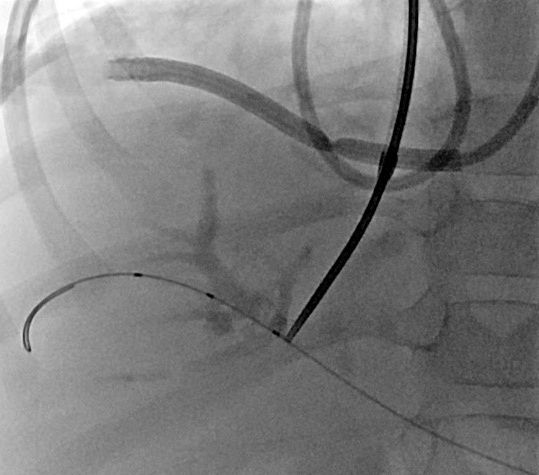

7 jähriger Junge mit Kurzdarmsyndrom und Leberzirrhose

Als Folgen des Pfortaderhochdrucks war die Milz vergrößert (Splenomegalie) und es traten Krampfadern der Speiseröhre (Ösophagusvarizen) auf. Um den Hochdruck zu entlasten wurde ein TIPS angelegt. Dazu wird aus der rechten Lebervene (A) mit einer speziellen Nadel ein Pfortaderast punktiert (B). Anschließend wird die Pfortader mit einem Draht sondiert (C) und die geschaffene Verbindung mit einem Ballon aufgedehnt und anschließend mittels Gefäßstütze (Stent) geschient (D). Durch diese künstliche Verbindung kann das Pfortadersytem deutlich druckentlastet werden.